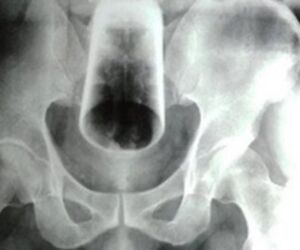

Homem enfia copo de vidro no ânus e é internado às pressas no Mato Grosso

Um homem precisou ser socorrido às pressas e foi levado ao Hospital Regional da cidade de Cáceres, no Mato Grosso, após introduzir um copo de vidro no ânus.

No entanto, ao chegar ao local, a equipe percebeu a gravidade da situação, pois o copo havia quebrado dentro dele. Ele foi submetido a uma cirurgia, mas seu estado de saúde ainda não foi divulgado.